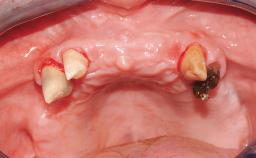

Immediate Loading of Eight Implants in the Maxilla and Six Implants in the Mandible and Final Restoration with Three-Unit and Four-Unit FDPs

Extensive scientific evidence has confirmed that immediately loaded implants with fixed full-arch provisional restorations can osseointegrate with success rates similar to conventionally or delayed loaded implants. A number of immediate-provisionalization techniques for edentulous jaws have been described. Some protocols differ when it comes to prefabricated provisional templates versus complete denture conversion; intrasurgical impressions versus direct relining; and cemented versus screw-retained provisional restorations. In this context, complete-denture conversion has been proposed for either intrasurgical impressions or direct relining. Another possibility is the utilization of a prefabricated provisional to be adapted either in the mouth (by direct relining) or in the laboratory (on a working model obtained from an intrasurgical impression).

Case Type Edentulous Maxilla

# of Teeth All

# of Implants 14